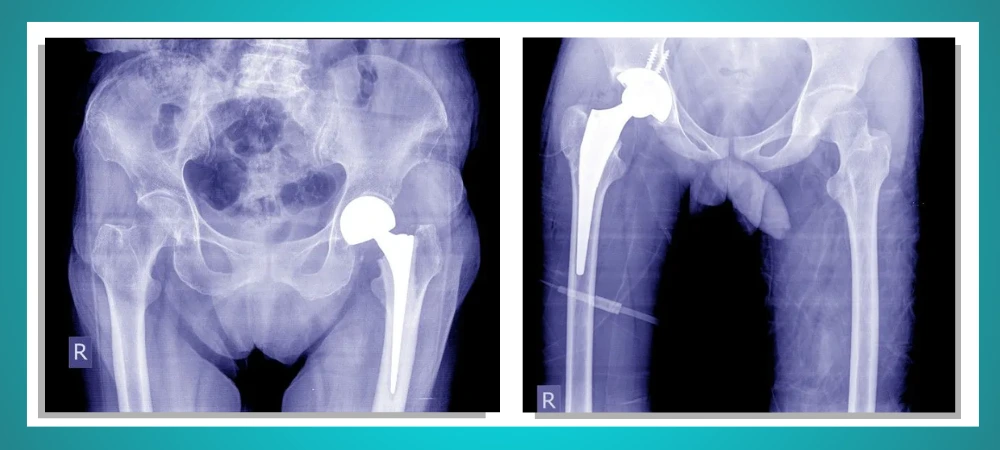

Hip Replacement in Patna involves replacing a damaged hip joint with an artificial one, often made from plastic and metal components. These artificial joints help reduce pain, improve functions, and make your life much easier.

Although arthritis is the most common reason for Hip Joint Replacement surgery, it also treats certain types of hip fractures and joint issues. Hip replacement surgeons recommend this surgery to their patients when all other treatment options fail to provide adequate relief from the pain. A Hip Replacement Surgeon in Patna uses two approaches to perform hip replacement that most people are unaware of.

To treat hip conditions such as severe osteoarthritis and hip fractures, Top orthopedic surgeons in Patna perform Hip Joint Replacement surgery. There are mainly two main approaches to performing these surgeries, which include: